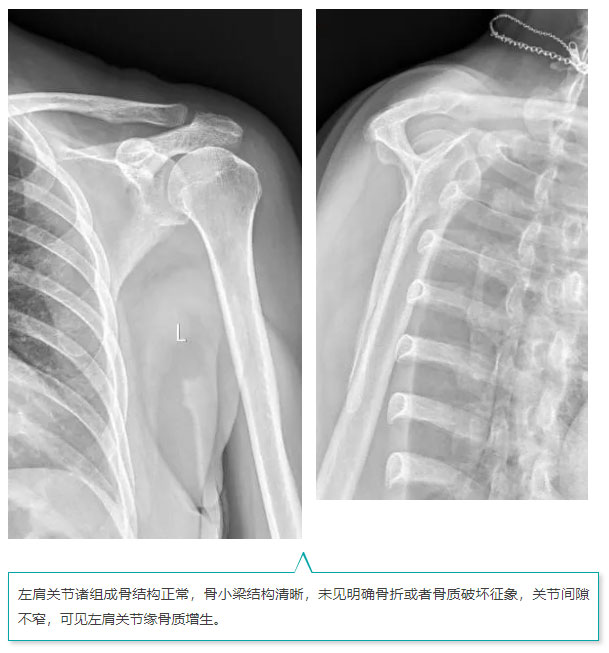

图像质量

*以上图像来源:西安医学院附属红会医院